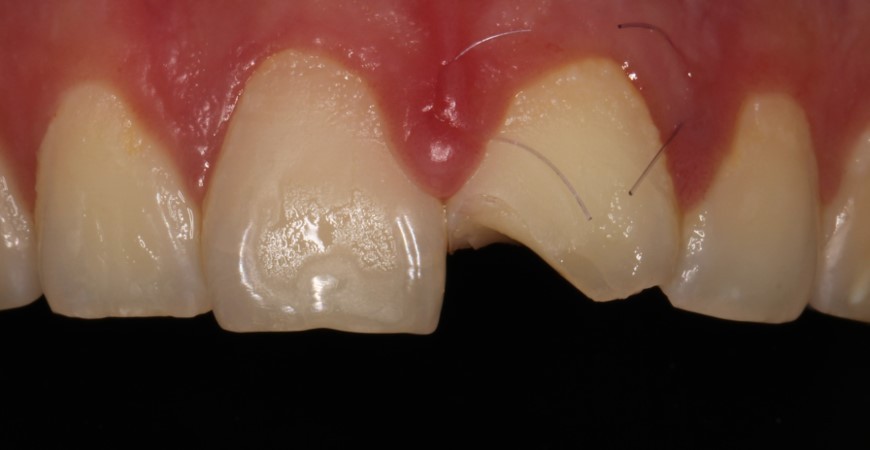

Спустя 6 месяцев после травмы окончательно отреставрировали 2.1 зуб. (фото после снятия коффердама, пациент больше не явился на осмотр)

Спустя 6 месяцев после травмы. (белая полоска около десны вследствие лечения в коффердаме)

Наблюдение: Фотографии спустя 1 год и 8 месяцев. 22.06.2024г.

Была проведена незначительная корректировка и отполировали до блеска

Фотография с поляризационным фильтром